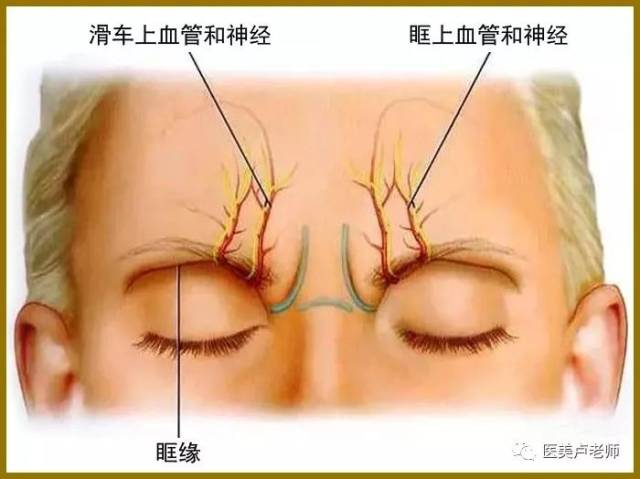

滑车上血管

皱眉肌纹的深面是滑车上动脉

1,眶上神经和滑车上神经